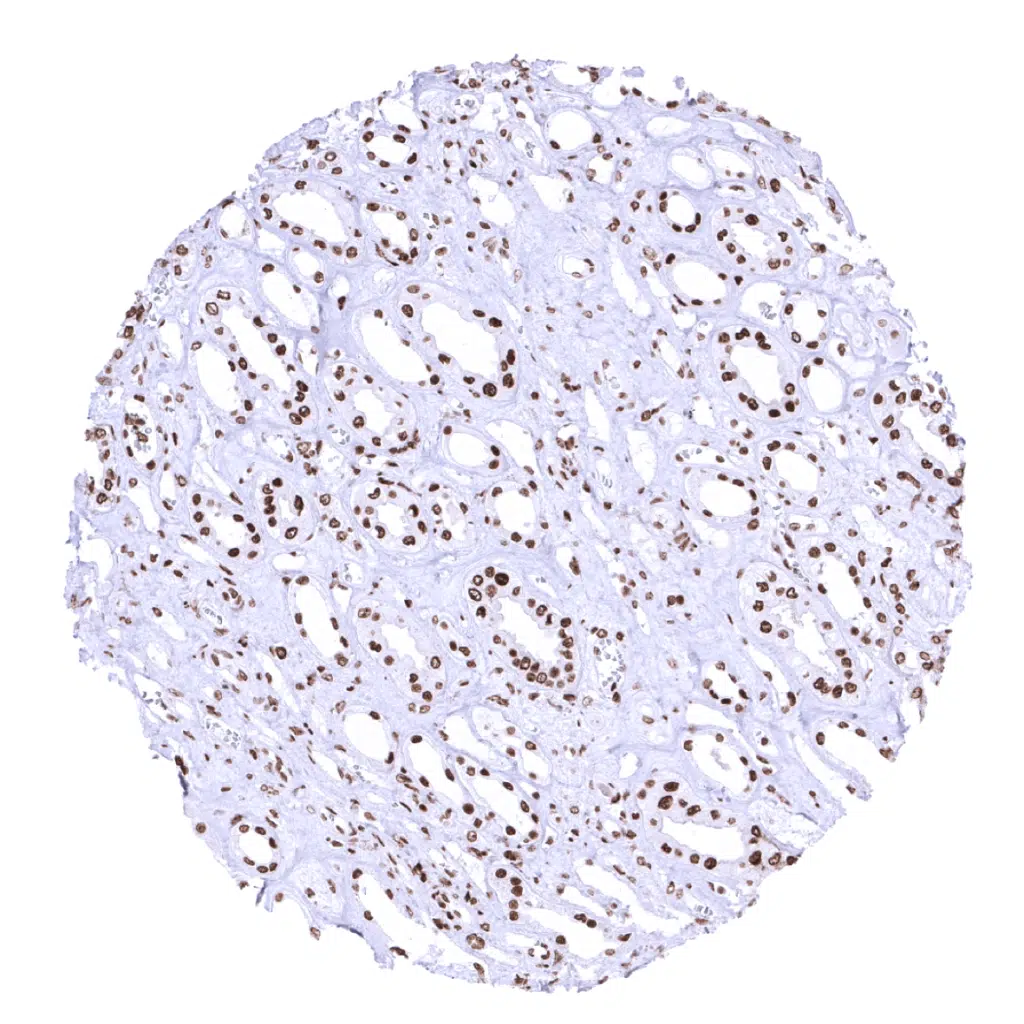

Kidney, cortex